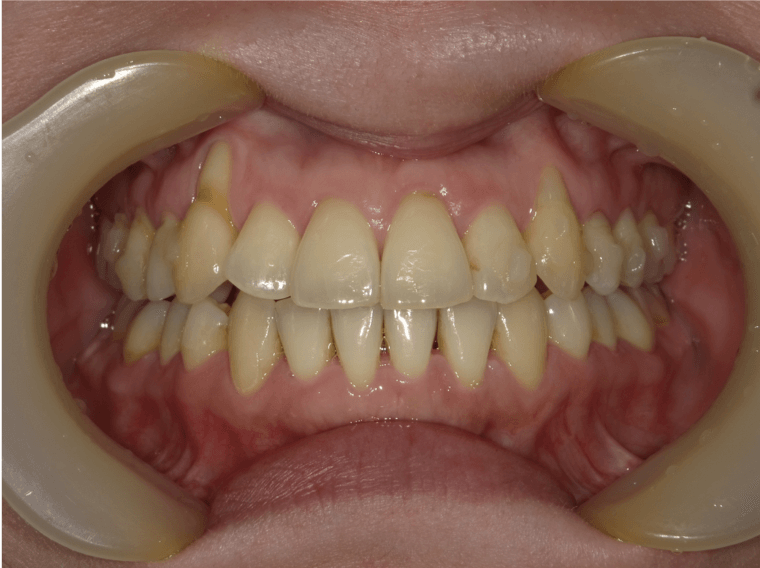

八重歯、重度叢生

BEFORE

AFTER

担当医コメント

左側八重歯があり、上下顎ともに重度の叢生である。歯を並べるスペースの確保を考えると抜歯を検討したが、患者の強い希望で非抜歯による治療を選択した。拡大とIPR、下顎前歯の唇側傾斜により、スペースの確保を計画しインビザライン治療を開始した。

年齢/性別

29歳 女性

主訴

上下ともに歯並びが悪い。非抜歯で治療して欲しい。

リスク

歯肉退縮が起こる可能性がある。

費用

85万円(矯正費用)

期間

4